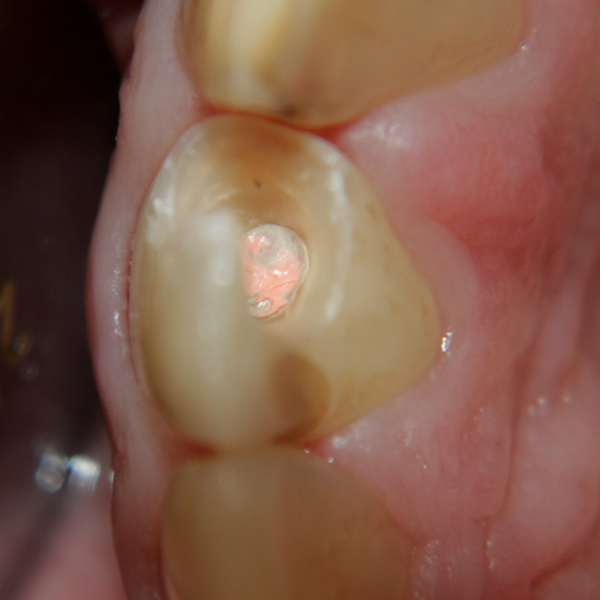

Директни възстановявания на странични зъби - поготовка на зъбите за възстановяване

Старите възстановявания са отстранени и кариесът е почистен. Необходимо е кариозната маса да се почисти радикално, тъй като при недобро почистване е възможен рецидив на заболяването. В областта на зъбния емайл това става когато оцветеният емайл се почисти до бяло; в областта на дентина е възможно да има радикално почистване дори и при наличието на оцветяване - просмукани пигменти в дентиновите каналчета, които пигменти произхождат от храни, кафе, кола, червено вино и т.н. Деминерализираният дентин е оцветен белезникаво и също не е необходимо да се изрязва - отстранява се само некротичният дентин и инфектираният дентин. При оставяне на некротичен дентин или кариозна маса няма как да подейства свързващата система - нито един бондинг агент не осъществява надеждна връзка с разпаднати материи.

Кариозната маса е почистена - виждат се обширни дефекти